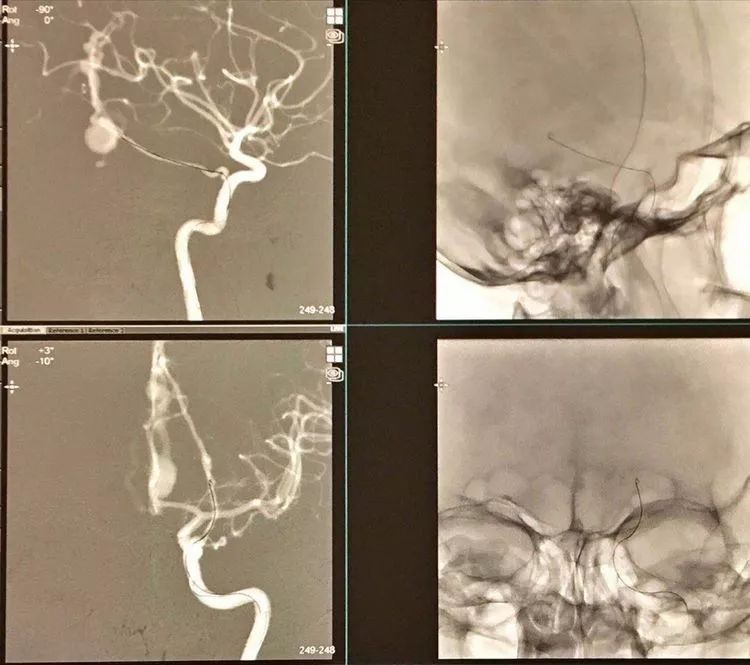

CASE 2 AN

-责任动脉直径约2mm,使用新型血流导向装置FRED Jr. 实现血流重构

-FRED Jr. 为双层支架,远端无导丝

CASE 3 AN

-左侧大脑中动脉大型动脉瘤,上干累及,较为细小

-采用Pipeline shield,4毫米直径的具有磷脂涂层FD,动脉瘤区域稍外膨,支架网丝密度更大可能有利于愈合

-重点是血流导向重构治疗动脉瘤和保留上干